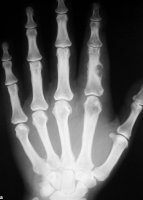

Um cisto ósseo epidermóide é uma lesão rara que ocorre quase exclusivamente nas falanges ou no crânio e se apresenta como uma lesão lítica ou um pseudotumor. Esses cistos geralmente aparecem nos pacientes, principalmente nos homens, com idades entre 25 e 50 anos. Eles são lesões benignas com evolução satisfatória após a excisão.

O cisto epidermóide é visto como uma lesão bem definida, com imagem osteolítica radiolúcida, com margem esclerótica envolvendo a falange. Estas características são bem ilustradas na mão de um adulto com cisto epidermóide nas figuras abaixo.